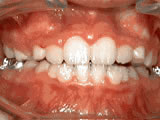

Open bite – Front teeth don’t touch

Patient sucked her thumb as a young child. She started treatment at age 13. She had braces and a special appliance — called a crib — to retrain the tongue, for 28 months. Now she can bite the lettuce out of a sandwich.